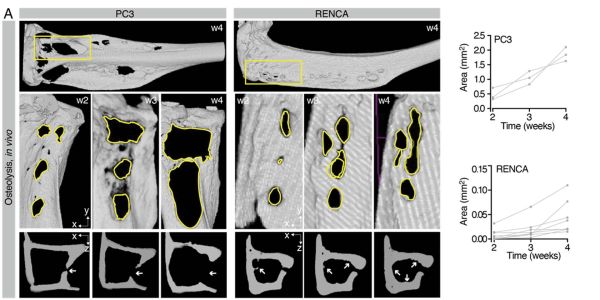

Digital twin potenziati dall’intelligenza artificiale destinati a rivoluzionare la ricerca sulle metastasi ossee

Un team internazionale, che comprende anche l'Università di Pavia, ha raggiunto un traguardo fondamentale nella ricerca oncologica, con uno studio appena uscito sulla prestigiosa rivista «Cancer Research».